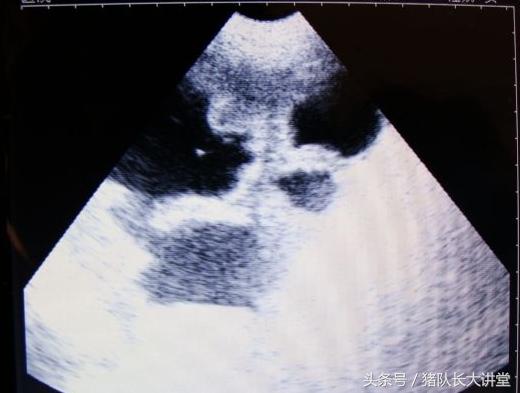

27天图

A、可以较为准确的测出是不是有小猪,具体使用办法,根据说明使用,大家也可以提出问题;注意,一般你检测有的就是有了,单是检测没有的时候应该多观察;

B、缺点,价格还是比较贵的,大家可以从不同渠道借下,但是要保证靠谱,不然误诊大了不如不测;